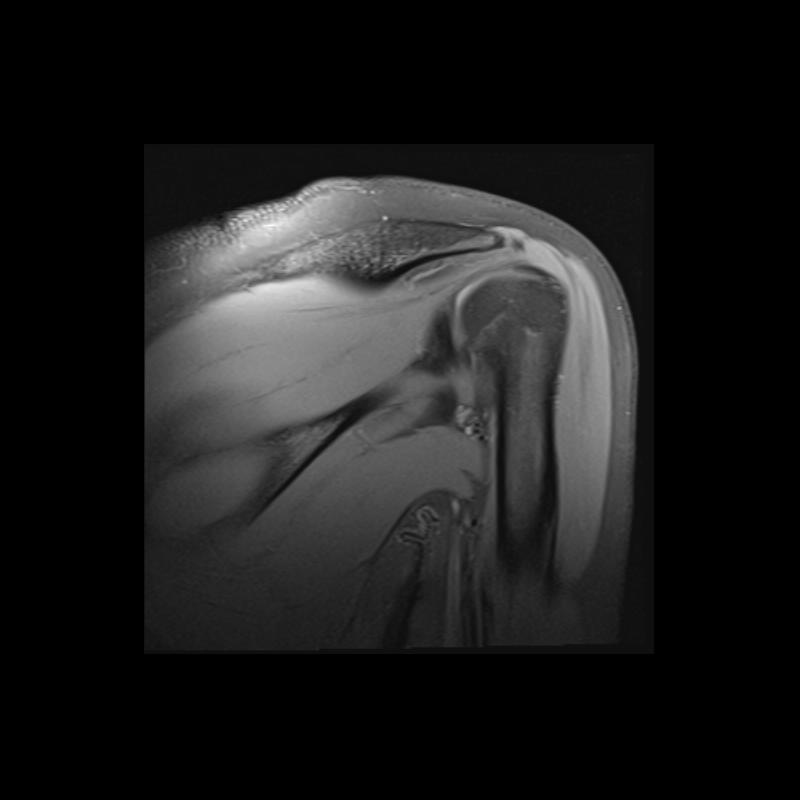

Shoulder MRI Anatomy